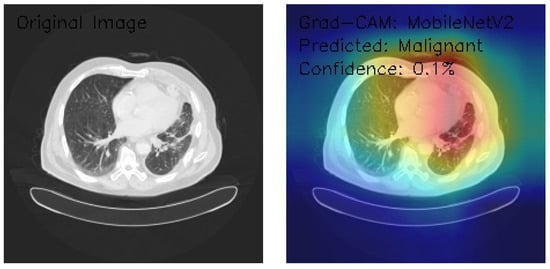

Analysis of MobileNetV2 Performance on Lung CT Images with Grad-CAM Visualization

This analysis focuses on three axial chest CT images evaluated using MobileNetV2 architecture, a deep learning model known for its efficient performance in image classification and feature extraction tasks. Grad-CAM was employed to understand the model’s decision-making process better. Grad-CAM is a visualization technique that highlights the regions of the input image the model considers most relevant for making predictions. This study assesses the model’s classification performance by integrating these advanced methodologies. It provides visual insights into the areas of the CT images that influenced its decisions, offering valuable interpretability to the outcomes.

Figure 12 shows the analyzed CT image displaying scattered nodular densities, suggesting potential pathological changes. Grad-CAM visualizations highlight bilateral peripheral activation, with strong attention to the posterior and lateral lung fields and notable emphasis on the mediastinal region. Despite identifying these features, the model classifies the image as Malignant with a confidence score of 0.0%, indicating a significant disconnect between feature recognition and classification confidence. This underscores the need for model recalibration and optimization of the classification layer to enhance decision-making reliability and ensure clinical applicability.

Figure 12.

Grad-CAM visualization using MobileNetV2 for lung CT scan with benign prediction. (Source: author’s analysis from data, 2024).

Figure 13 shows the CT image exhibiting interstitial markings, potentially indicative of underlying pathology. Grad-CAM visualization displays a diffuse activation pattern, predominantly focusing on the central and right lung fields, with distinct color gradations suggesting varying feature importance. The model classifies the image as Benign with a confidence score of 0.0%, reflecting uncertainty in its decision-making process. While the activation patterns highlight relevant anatomical regions, the low confidence score points to the need for recalibration of the model’s classification layers and confidence metrics to improve reliability and clinical applicability.

Figure 13.

Grad-CAM visualization using MobileNetV2 for lung CT scan with malignant prediction. (Source: author’s analysis from data, 2024).

Figure 14 shows the model classifying the image as Malignant with a slightly improved confidence level of 0.1%, although still insufficient for reliable diagnostic decision-making. The activation pattern suggests the model detects potentially significant features, but the marginal increase in confidence underscores persistent challenges with classification certainty. Further calibration of confidence scoring, refinement of the classification layer, and additional training data may be necessary to enhance model reliability and clinical usability.

Figure 14.

Grad-CAM visualization of MobileNetV2 for lung malignancy prediction with a 0.1% confidence improvement. (Source: author’s analysis from data, 2024).

This analysis evaluates three axial chest CT images processed by the MobileNetV2 architecture, leveraging Grad-CAM visualizations to assess model attention and classification. Image 1 highlights scattered nodular densities with bilateral peripheral and mediastinal activation, classified as Malignant with 0.0% confidence. Image 2, demonstrating interstitial markings, shows diffuse central and right lung activation, classified as Benign with 0.0% confidence. Image 3, featuring clear lung parenchyma, exhibits asymmetric activation in the right upper lung, classified as Malignant with a slightly higher confidence (0.1%). The model’s confidence levels remain critically low despite consistent feature detection and focused attention patterns, indicating calibration and classification inefficiencies.

Key findings reveal MobileNetV2’s sensitivity to anatomical variations and clear feature recognition but with limited reliability for clinical applications. Recommendations include the recalibration of confidence metrics, architecture-specific optimizations, and validation through ensemble methods and expert radiological input. These refinements address classification uncertainty and enhance the model’s applicability to lung CT image analysis.